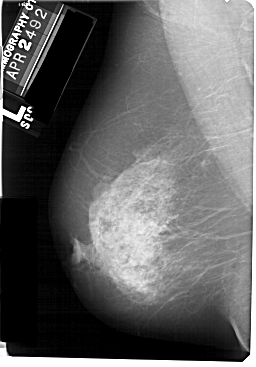

A_1127_1.LEFT_MLO

LEFT_MLO LINES 5491 PIXELS_PER_LINE 3826 BITS_PER_PIXEL 12 RESOLUTION 43.5 NON_OVERLAY